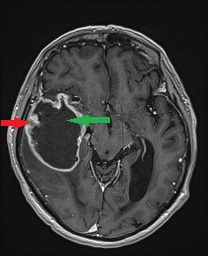

- Zmiany naczyniowe (np. naczyniaki jamiste, tętniaki)

- Zmiany infekcyjne (np. ropnie, gruźlica, zakażenia grzybicze, pasożytnicze)[1–4]